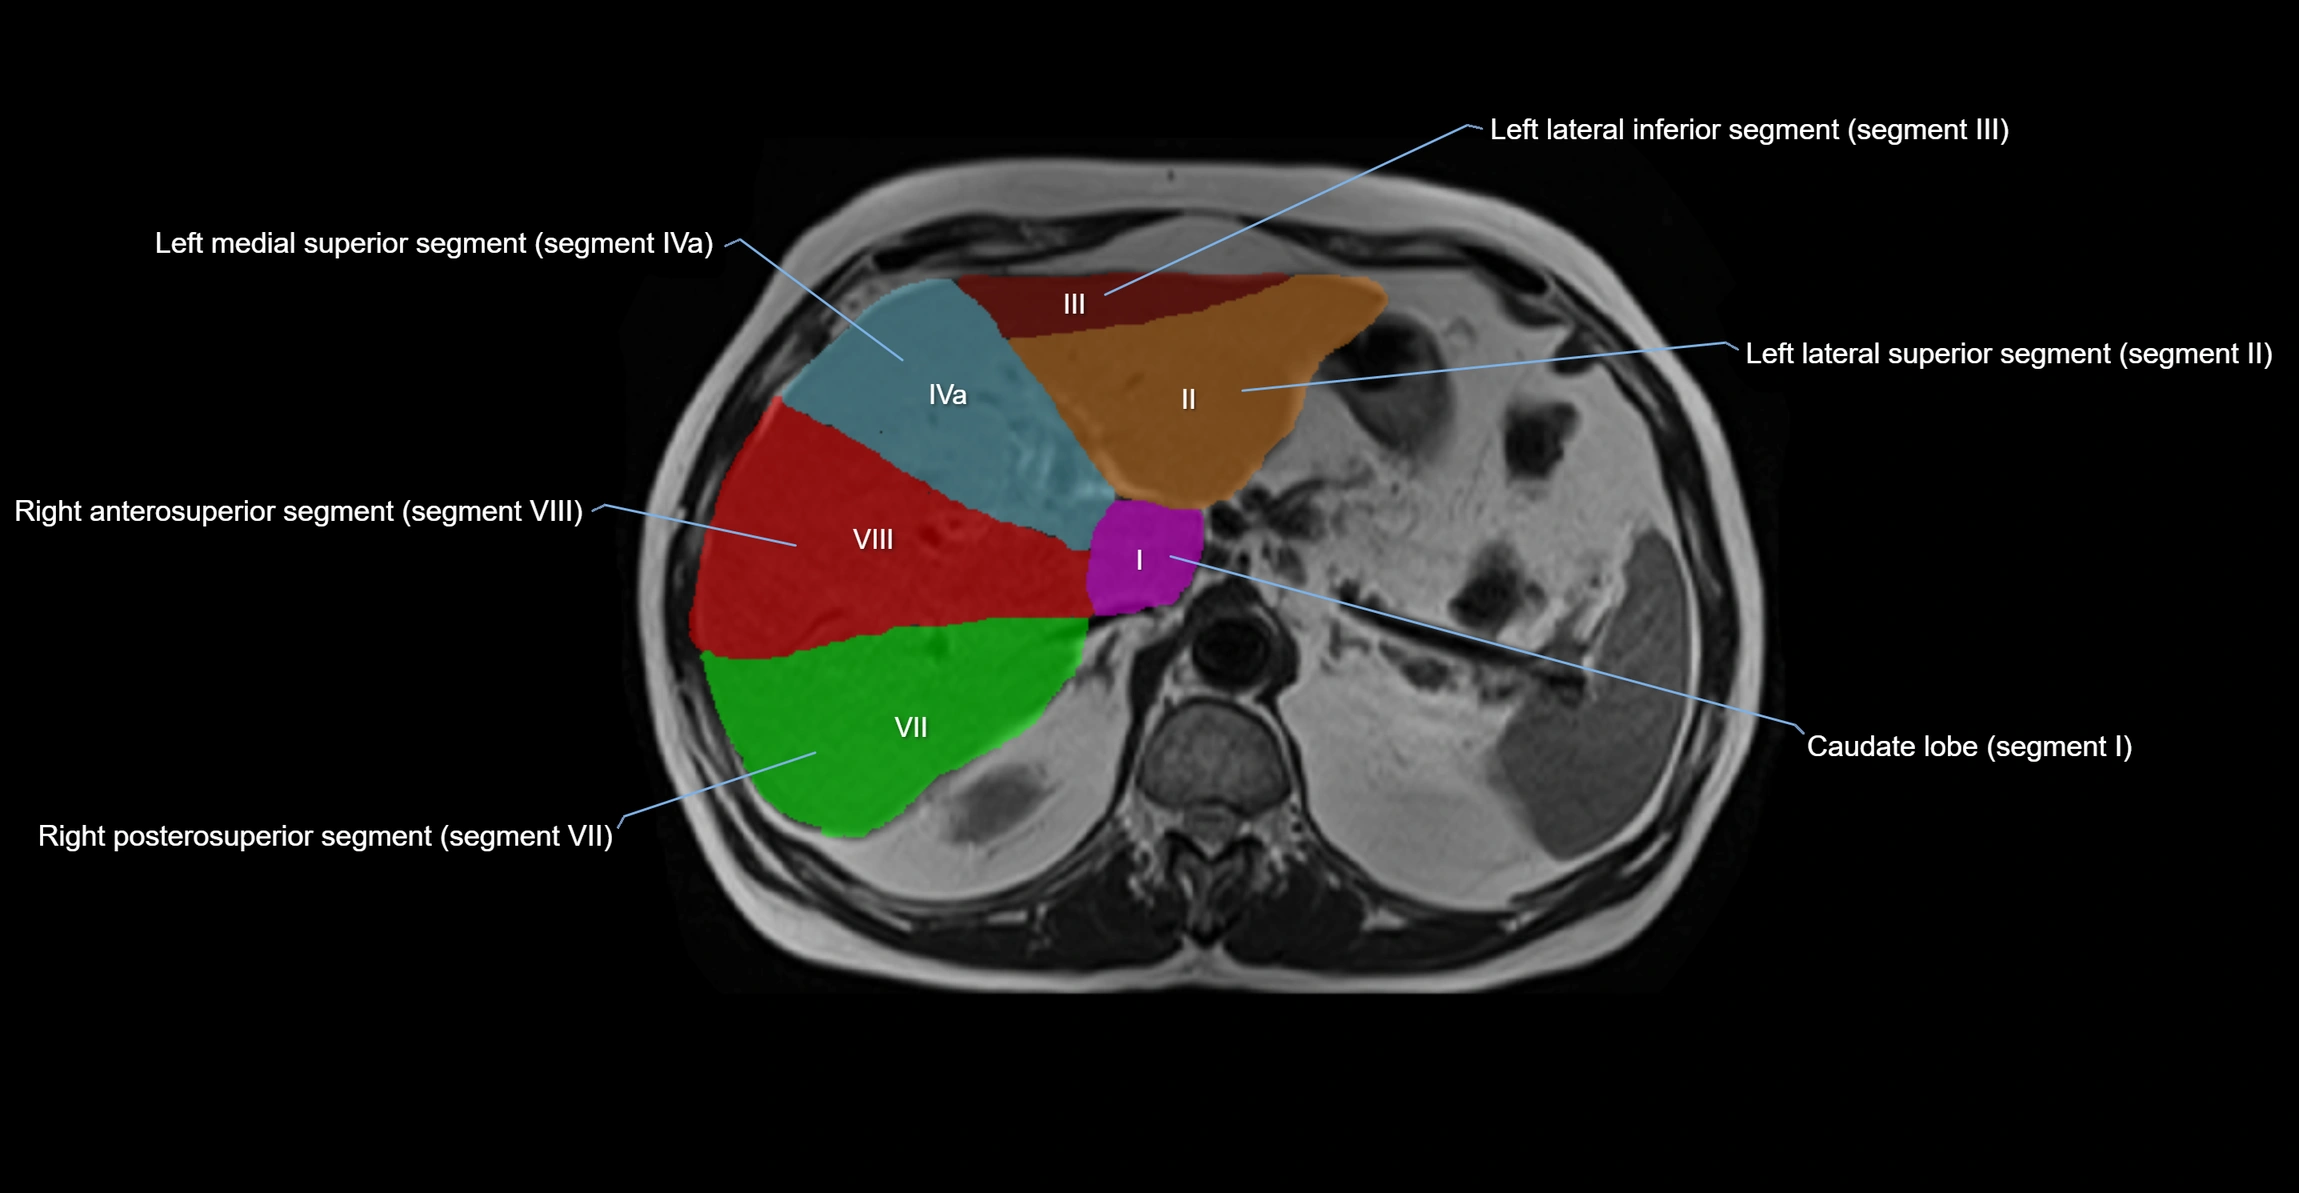

The caudate lobe of the liver is a distinct anatomical subdivision of the liver, designated as segment I in Couinaud’s classification. It lies on the posterior surface of the liver, between the fissure for the ligamentum venosum (left boundary) and the groove for the inferior vena cava (IVC) (right boundary). Superiorly, it is related to the posterior liver surface, and inferiorly it is separated from the left lobe by the porta hepatis.

The caudate lobe is unique because it receives dual portal venous and arterial inflow from both the right and left portal veins and hepatic arteries. It also has independent venous drainage directly into the IVC via multiple small hepatic veins, unlike other lobes that drain through the three main hepatic veins.

• Segment I (Couinaud classification)